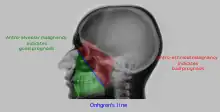

Maxillary sinusitis[2] | ![]() Differentiating pathology in maxillary sinus

Polyp |

Malignancy |

![]() Onhgren's line